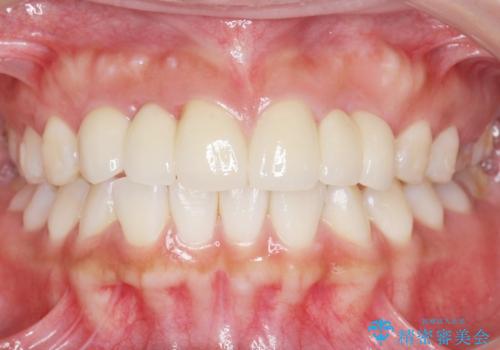

自然な仕上がりにご満足頂けました。

治療終了後、奥歯に残っていた矯正の接着剤を除去し、ホワイトニングも行いました。

クラウンの種類:オールセラミッククラウン スタンダード